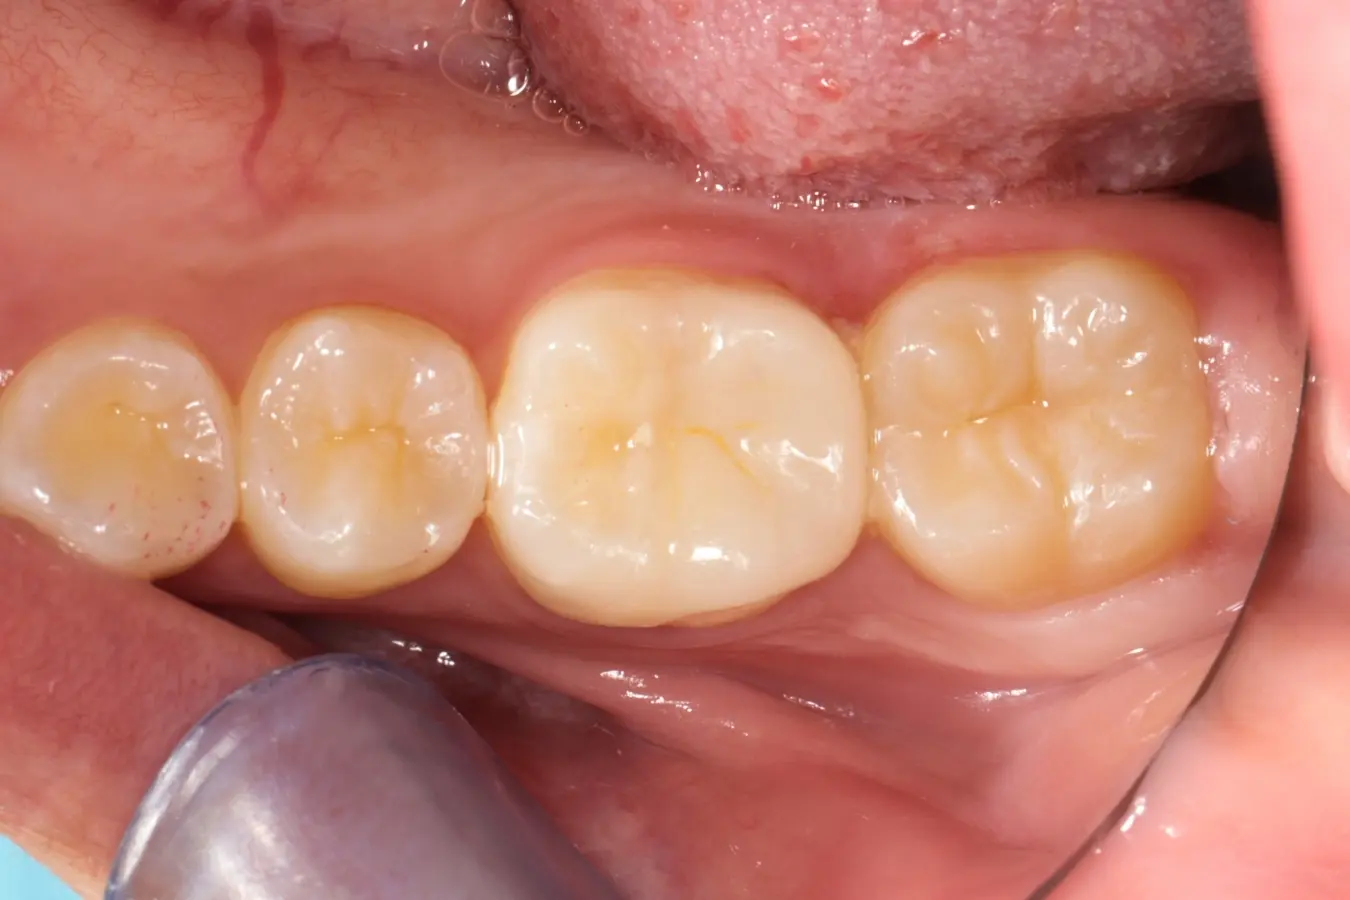

• 術前 43

術後 41

牙橋

主治醫師

• 楊明憲

治療時間

約1年4個月

主訴

吃東西左邊後牙會痛